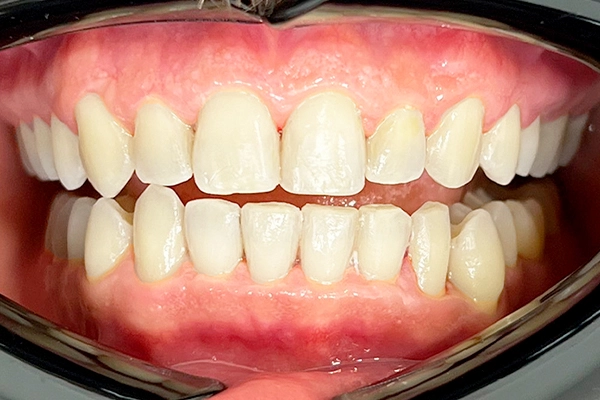

Conoce el antes y después de nuestros tratamientos